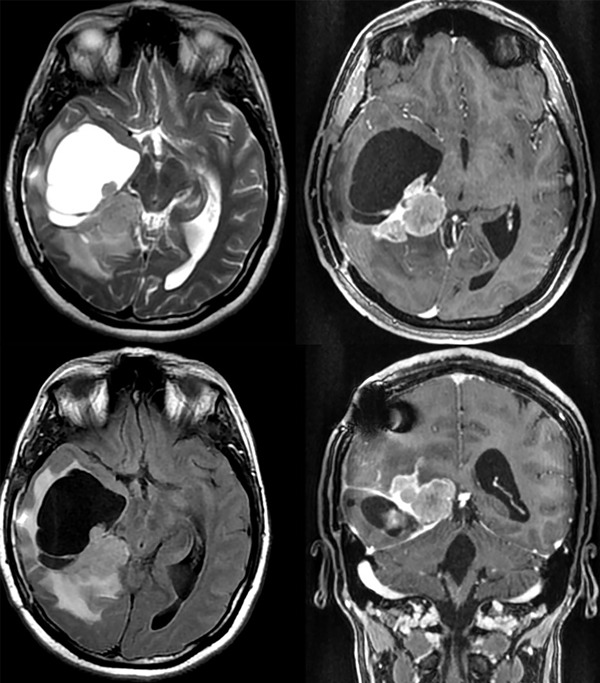

En sucesivos controles la paciente presenta un deterioro de su estatus previo, con signos clínicos de hipertensión endocraneana (cefalea y episodios aislados de náuseas y vómitos), por lo que se indica una nueva RM. La resonancia es realizada a los cinco meses de la intervención quirúrgica (Figura 4).

Figura 4. Se observa una importante recidiva de la masa tumoral con efecto de masa y secuestro ventricular temporal derecho.

Sobre la base de los hallazgos clínicos y de imágenes, se programa una reintervención quirúrgica. La paciente evoluciona de manera muy favorable, incluso con menor impacto en la clínica cognitiva/conductual en comparación con la intervención previa. Se logra una nueva resección satisfactoria, aunque por las características de las imágenes y el comportamiento clínico, se comienza a dudar del grado de la OMS dado previamente a la lesión. Se va de alta al cuarto día postoperatorio, sin déficits agregados.

La anatomía patológica de esta nueva resección informa proliferación neoplásica de estirpe astroglial de celularidad moderada a intensa, con figuras de mitosis atípicas y pequeños focos de necrosis, constituyendo ahora un XAP-A grado 3 de la OMS, con un índice de proliferación (Ki67) del 20%.